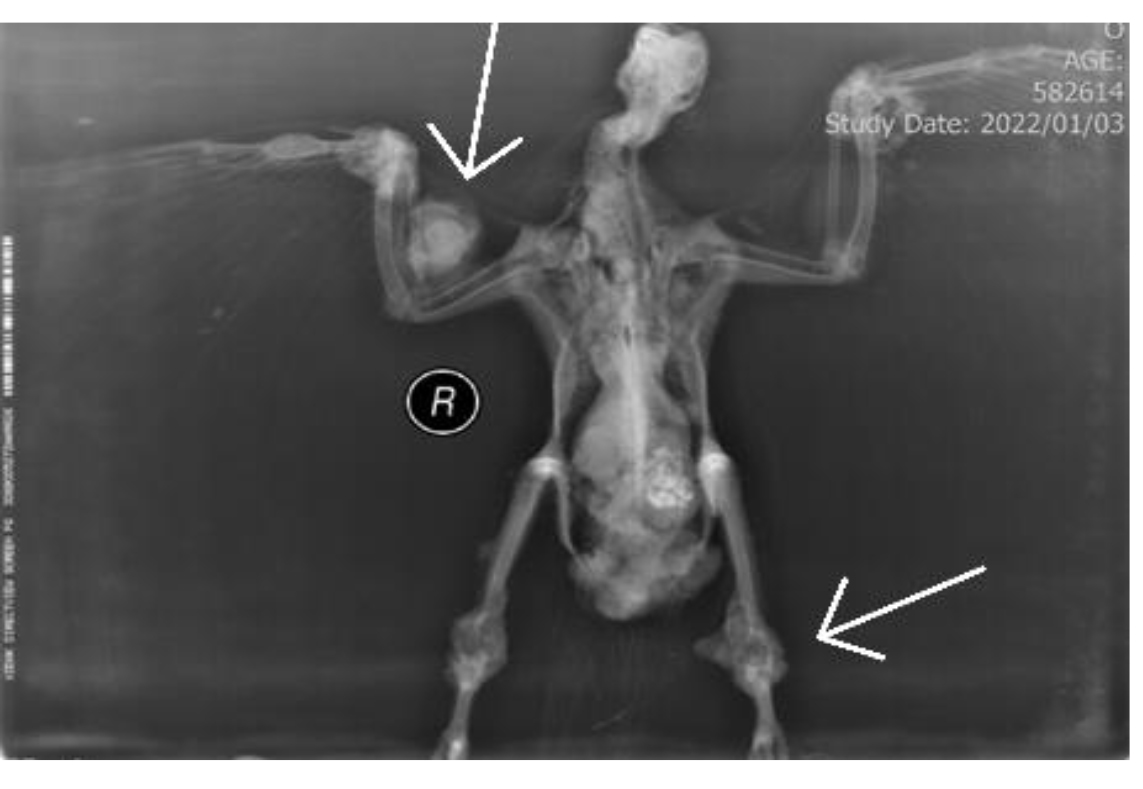

The most common radiographic findings were periarticular inflammation, followed by renomegaly, polyostotic lesions, hepatomegaly, air sacculitis, pneumonia, and gastroenteropathy (Figure 5) (Table 2).

Figure 5. Radiographic image of a pigeon suspected of tuberculosis in the V.D position, showing polyostotic lesions and articular swelling in legs and wings.

Radiographic findings number (out of 12) Percentage (%)

Peri-articular inflammation 8 66.66%

Renomegaly 7 58.33%

Polyostotic lesions 7 58.33%

Hepatomegaly 6 50%

Air sacculitis 6 50%

Pneumonia 3 25%

Gastroenteropathy 2 16.66%

Table 2.Prevalence of radiographic findings in pigeons suspected with tuberculosis.